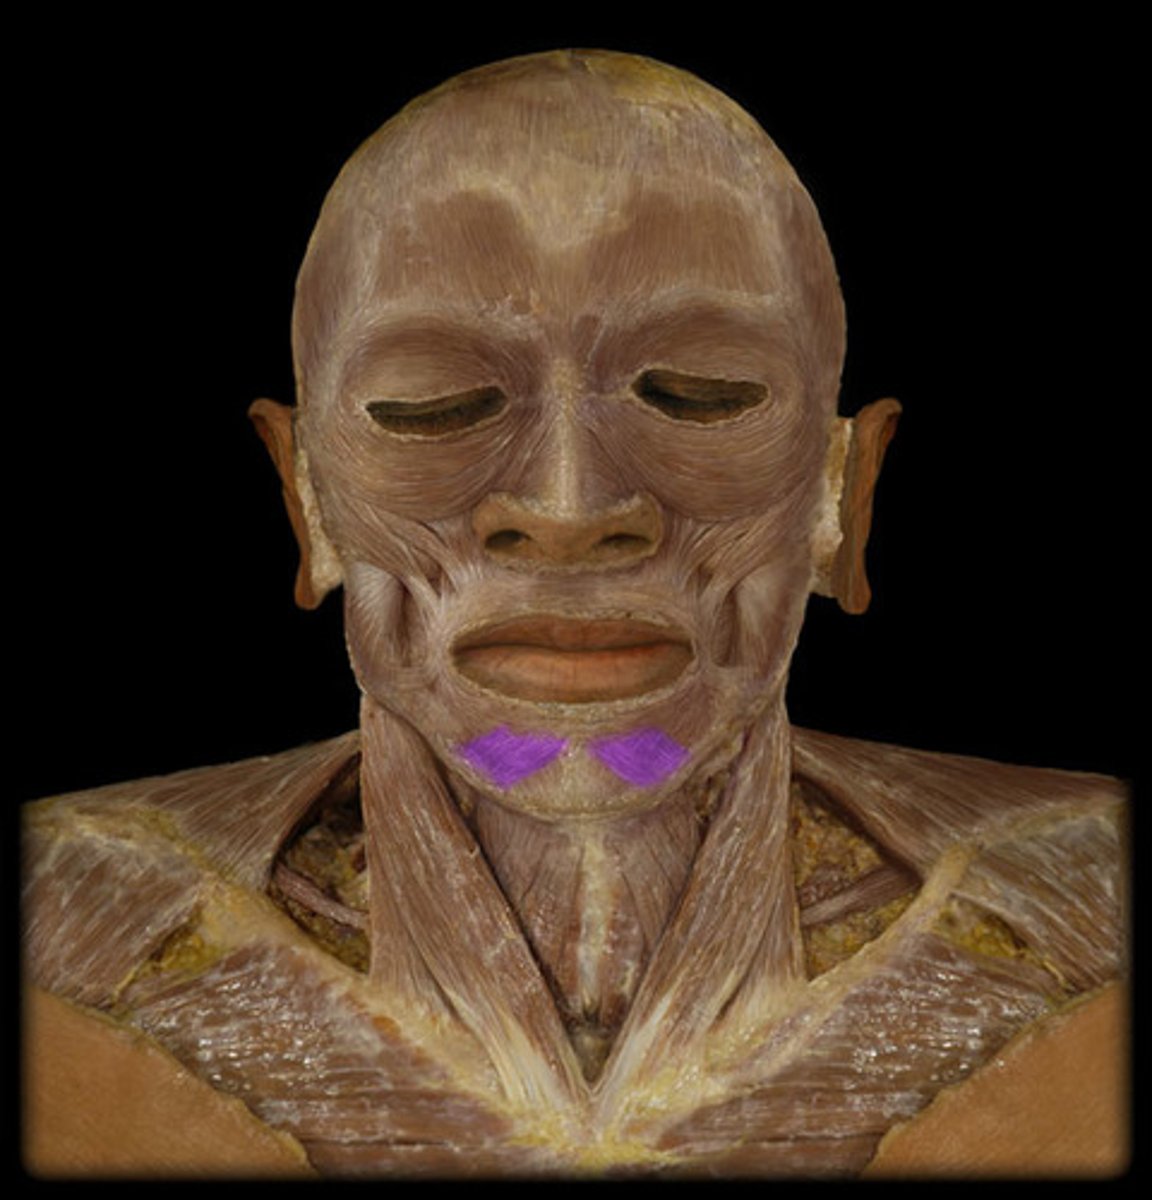

Platysma